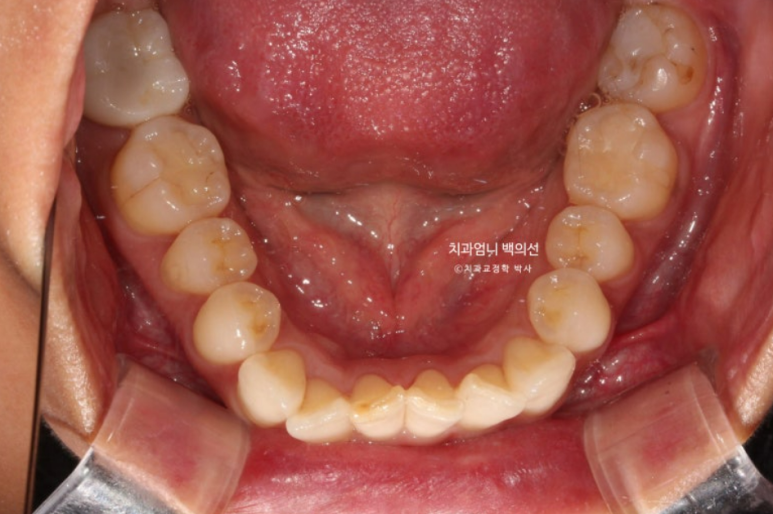

23년 9월 교정치료를 이해 내원하신 분입니다.

고치고 싶은 것은 3가지 입니다.

덧니, 비대칭, 입이 잘 안다물어지는 것

위 아래 앞니 중심선 불일치가 보입니다.

엑스레이를 찍어보면 뼈의 비대칭은 없으나 덧니때문에 위 앞니 중심선이 한쪽으로 쏠려서 비대칭감을 느끼는 상태입니다.

입천장으로 들어가있는 측절치는 아랫니와 반대로 물리는 반대교합 입니다.

덧니가 심하고 입이 잘 안다물어 지기는 하지만 입매 분석시 입술 돌출이 없어서 작은어금니 발치는 하지 않았습니다.

대신 사랑니 공간이 충분해서 사랑니 공간으로 어금니 후방이동을 통해 덧니를 배열하기로 합니다.